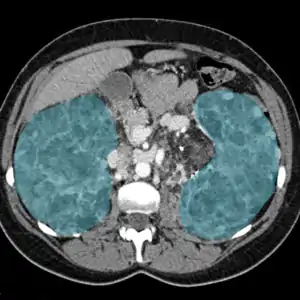

Nefrite (do grego - nephrós - rim + itis - inflamação, pelo latim nephrite), também chamada nefroflegmasia (forma em desuso), consiste na inflamação dos rins, responsável por metade dos problemas renais.[1]

Resulta de processo de inflamação disseminado no Nefron que podem atingir os glomérulos (estrutura renal em forma de novelo e responsável pelo trabalho de filtração neste órgão[2]) (Glomerulonefrite), e tem por base uma reação imunológica ou outra infecção (como na pielonefrite).[3]